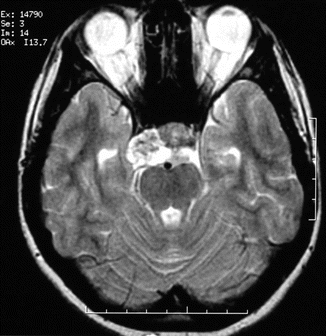

Fig. 45.5

Axial T2-weighted image of a 17-year-old girl with clivus chordoma shows a heterogeneous mass in the upper part of the clivus extending to the right cavernous sinus